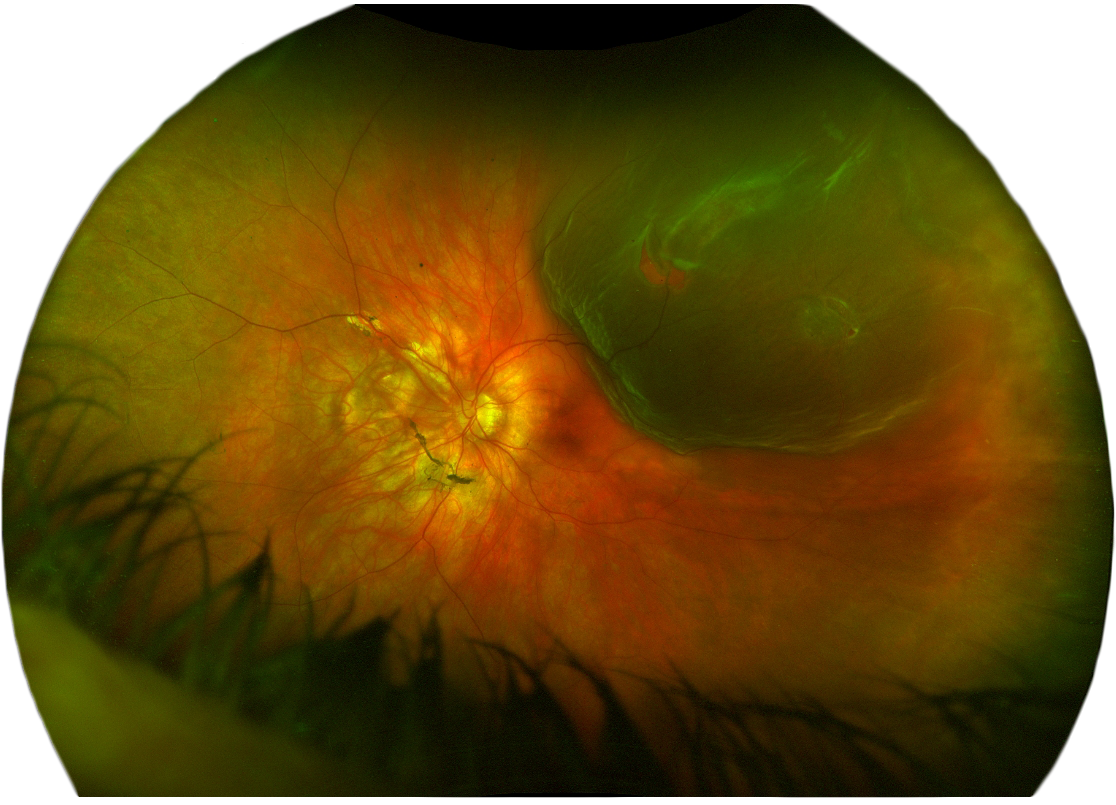

www.retinesud.frDécollement Rétine

www.retinesud.frDécollement Rétine